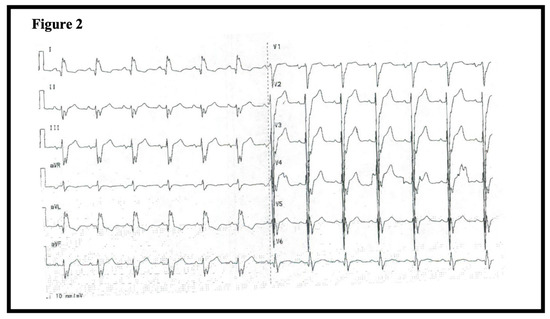

At the time of admission in 2011, the patient was hemodynamically stable (blood pressure 116/69, heart rate 100) and presented with a fever leading to initiation of antibiotic treatment due to suspicion of pneumonia. Routine blood testing including cardiac troponins, hematological, and kidney biomarkers were unremarkable. However, an ECG showed intraventricular conduction defect with a QRS-duration of 150 ms (Figure 2). A chest radiograph revealed cardiomegaly (Figure 3A). Subsequently, an echocardiography demonstrated severe left ventricular (LV) dilation with an end-diastolic diameter of 82 mm (indexed 41 mm/m2) and a LV ejection fraction (EF) of 10% (Figure 3B). These findings led to the initiation of anti-congestive medical treatment and later implantation of a cardiac resynchronization therapy-defibrillator. Further diagnostic work-up included genetic screening, right heart catheterization, and coronary angiography. The right heart catheterization showed a reduced cardiac index (1.8 L/min/m²) and elevated cardiac chamber filling pressures (right atrial pressure of 12 mmHg, mean pulmonary artery pressure of 47 mmHg, and wedge pressure of 31 mmHg). The coronary angiogram was normal, and the myocardial biopsy showed histologic features consistent with dilated cardiomyopathy with severely hypertrophic cardiomyocytes (Figure 4A–C).

Figure 2.

ECG of patient 1 at admission time showing an intraventricular conduction defect.